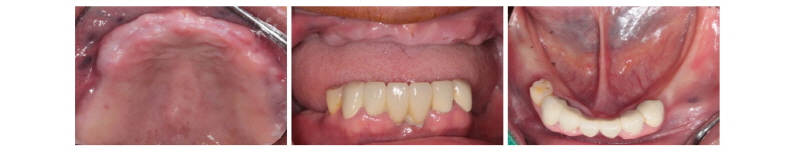

본 59세 여환은 양쪽 위, 아래 큰 어금니가 흔들리고 잇몸이 부었으며 왼쪽 아래 큰 어금니는 오랫동안 없었다는 주소로 본원에 내원하여 임상 및 방사선학적 검진 결과 아래와 같이 관찰되었다. #33 치아는 Mob (+++) Per (+)와 bone loss, #16, 26, 46 치아는 Mob (++/+++) Per (+)와 bone loss, #36, 37 치아는 missing 상태였다. 이에 #16, 26, 33, 46 치아는 hopeless teeth, #17, 36, 37, 47 치아는 missing teeth로 진단되었다(Fig. 19). #16, 26, 33, 46 치아는 발치 후, #i16, i17, i26, i33, i36, i37, i46, i47에 implant 식립과 #i16, i17, i26에 sinus lifting 및 #i33, i46, i47에 GBR을 계획하였다. #i36, i37은 flapless implant surgery 및 immediate loading을 계획하였다. #16, 26, 33, 46 치아를 발치하였고, 2개월 후에, 상, 하 rubber impression 채득 후, stone model 제작하였다. 또한 arch 전용 tray를 bite한 상태로(Fig. 20, 21) CBCT 촬영을 하였다(PHT-30LFO, VATECH). 이후 CBCT 영상과 alveolar ridge와 soft tissue model을 scanning한 영상(TRANSFORMER, Megagen)을 정합하였다. 새로운 영상을 바탕으로 #i36, i37 위치에 implant fixture 식립과 customized abutment와 provisional bridge를 design하였다(R2GATETM, Megagen, Fig. 22, 23). Design대로 3D printer (Perfactory Digital Dental Printer 3, EnvisionTEC) 통해 surgical guide를 제작하였고(Fig. 24) milling machine (TicamPro and WhitecamPro, Megagen)으로 customized abutment와 provisional bridge를 milling하였다(Fig. 28). 임플란트 수술은 5회에 걸쳐서 진행하기로 하였다. 첫 번째 수술일에는 #i36, i37 fixture 식립과 동시에 abutment 체결과 provisional bridge를 합착하였다(Fig. 25-27, 29). 이후, 1개월 후에 #i16, i17 fixture 식립과 lateral approach로써 sinus lifting을 시술하였다. 3개월 후에 #i36, i37에 최종 인상 채득하여 도재금관 수복을 하였다(Fig. 30, 31). 향후 남은 부위에 임플란트 수술 및 보철 진행 예정이다.

Fig. 25. Intraoral photo taken before surgery. |

Fig. 26. Surgical guide positioned on mandible. |

Fig. 27. After surgical drilling sequence, fixture was installed on each site. |